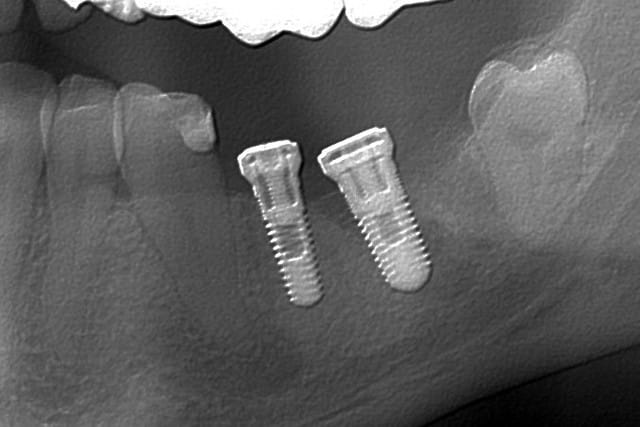

Débutant en implanto, j'ai un cas à vous soumettre, pour lequel je me pose des questions.

Patient mâle, 35 ans. 46 extraite en mai 2009, suite à une fracture médiane. Veut remplacer par un implant plutôt qu'un bridge. Jusque là, fastoche.

Sauf que, sur le scan, je vois deux trucs qui me dérangent:

1/ On voit encore 'achement bien les alvéoles, des mois après l'extraction. Certes elles sont comblées mais quand même, y'a une sacrée différence de densité avec le reste de l'os.

Est-ce que l'os est assez dense néanmoins pour implanter ?

2/ Késako que le machin radio opaque qui longe la paroi osseuse linguale ? Ca a tout du dépassement mais en ressortant la radio de la dent fracturée, ça avait l'air plutôt propre.

Est-ce que ça risque de poser problème pour l'ostéointégration ?

Je suis chez Straumann. Je compte mettre un 4.8 en Wide Neck. Pour la longueur par contre, je dépasserais pas 10 si je veux respecter à peu près l'axe des dents adjacentes.